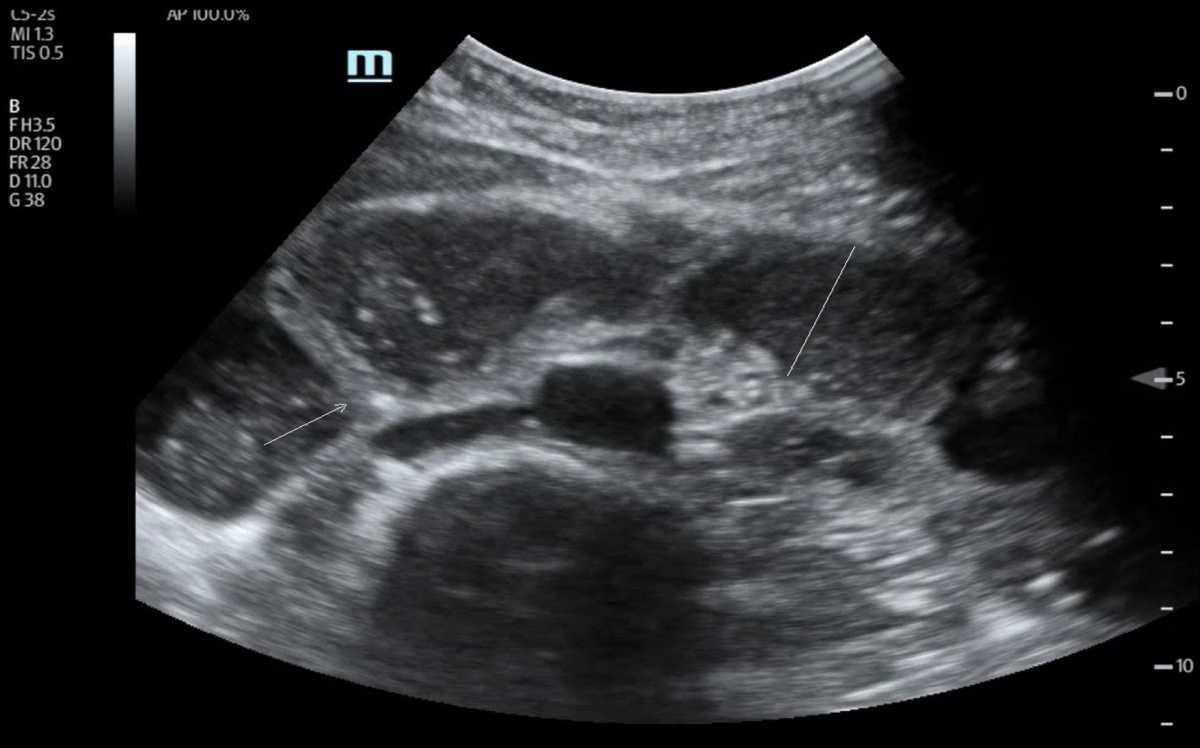

- Dilatation des anses grêles : diamètre > 25 mm (> 2,5 cm), contenu liquidien, paroi fine.

- Anses coliques : plus périphériques, contenu gazeux, haustrations visibles.

💧 Rechercher un épanchement inter-anse : marqueur de souffrance digestive.